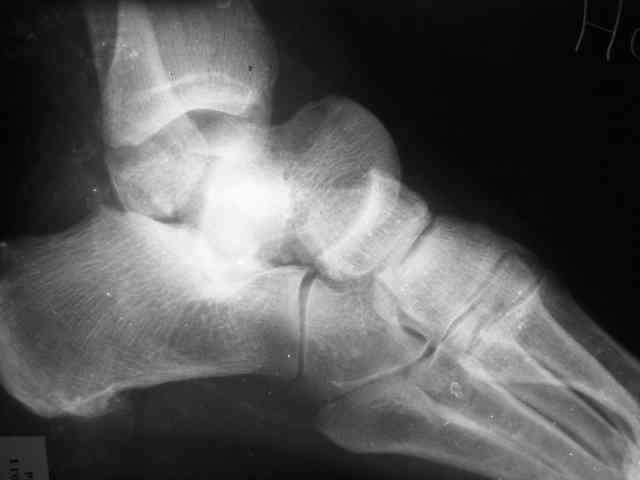

Уважаемый Александр! Как обещал представляю Р-граммы и операционные фото.

Ваши (лично ваши) рекомендации - астрагалэктомия-аппаратный пяточно-большеберцовый артродез с одновременным удлинением голени - правильно?

При столь массивном секвестре (блок таранной кости), длительная антибиотикотерапия только губит естественную флору и помогает селекции

Стабильность дает возможность расти сосудам. При хорошем кровоснабжении смежных фрагментов это все, что надо. А здесь есть большой секвестр. Разумно ли ждать, пока он васкуляризуется? Очевидно, без некрэктомии проблему не решить.